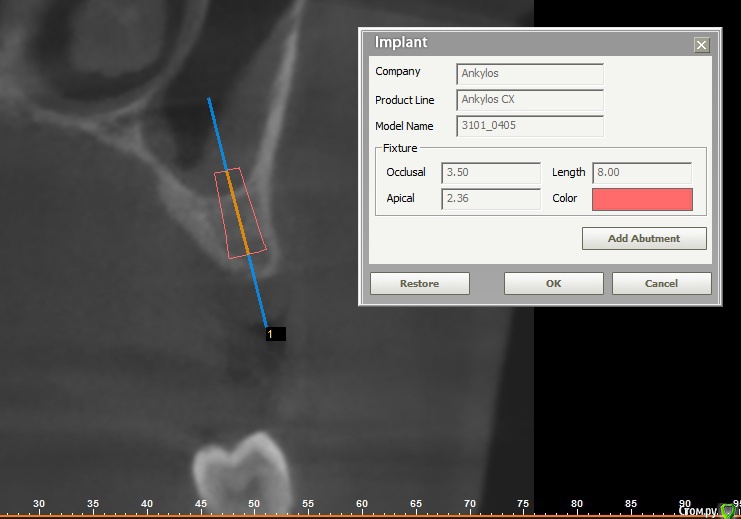

roberttm Опубликовано 26 ноября, 2015 Поделиться Опубликовано 26 ноября, 2015 Доброго времени суток, уважаемые знатоки и профессионалы. Наконец-таки, спустя более чем пять лет после удаления зуба, решился и кое-как начал предпринимать первые шаги на пути к имплантации Отсутствует зуб на верхней челюсти, за клыком. Сделал КТ. Костной ткани немного, как по высоте, так и по толщине. Был в двух клиниках, врачи дают разные рекомендации и, соответственно, планы лечения - я несколько растерялся, Первый вариант: сделать костную пластику (подсадку), установить имплант Dentium высотой 5 мм. Второй вариант: сделать костную пластику (подсадку), открытый синуслифтинг, установить имплант MIS высотой 8 мм. С одной стороны, я, как дилетант, согласен с позицией, что имплант высотой 8мм будет более устойчивым по сравнению с 5мм. Но в первой клинике врач заверил, что якобы есть клинические испытания и доказано, что имплант выстой 5мм ничуть не хуже по устойчивости по сравнению с имплантом высотой 8 мм и выше. Так ли это? Плюс ко всему за счет того, что нет необходимости в открытом синуслифтинге, суммарные затраты первого варианты выходят ниже второго.В общем я в растерянности и прошу высказать свое мнение. Ссылка на комментарий

carloss Опубликовано 29 ноября, 2015 Поделиться Опубликовано 29 ноября, 2015 Можно поставить 5-6 мм имплантат, не больше 3,5 диаметр, с небольшим мягким синус -лифтингом, без костной пластики, можно обойтись десневой. Но, для того, чтобы кость по шейке в дальнейшем сильно не рассасывалась, ее нельзя скелетировать в процессе, что в общем не очень просто и не все хирурги владеют этой техникой. 2 Ссылка на комментарий